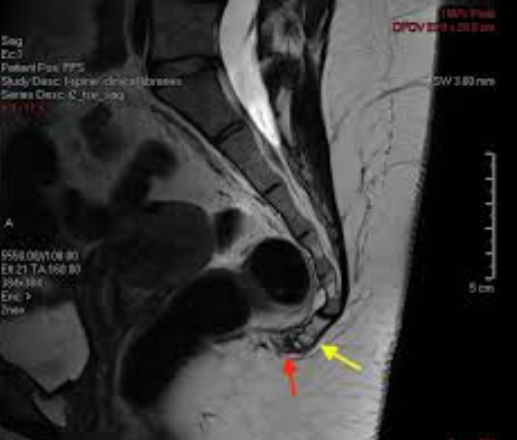

MRI상 꼬리뼈부위의 전이암

영상 검사: X-ray, CT, MRI 등을 통해 골절, 탈구, 감염, 종양 여부 등을 평가

x-ray 및 MRI상 골절등을 확인.